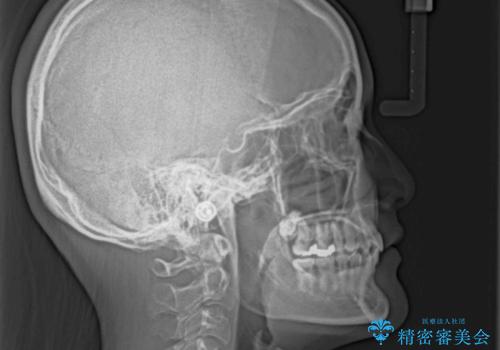

下顎の装置が頻繁に脱落し、治療は難航しましたが、当初予定の2年間で無事に治療を終えることができました。

奥歯の咬み合わせは上顎に対して下顎が後方位にあり、上顎前歯で下顎前歯が隠れるような典型的な過蓋咬合です。

補助装置を用いて上顎大臼歯を後方に移動させながら、ワイヤー装置で歯列を整えて深い咬み合わせを挙上することとしました。